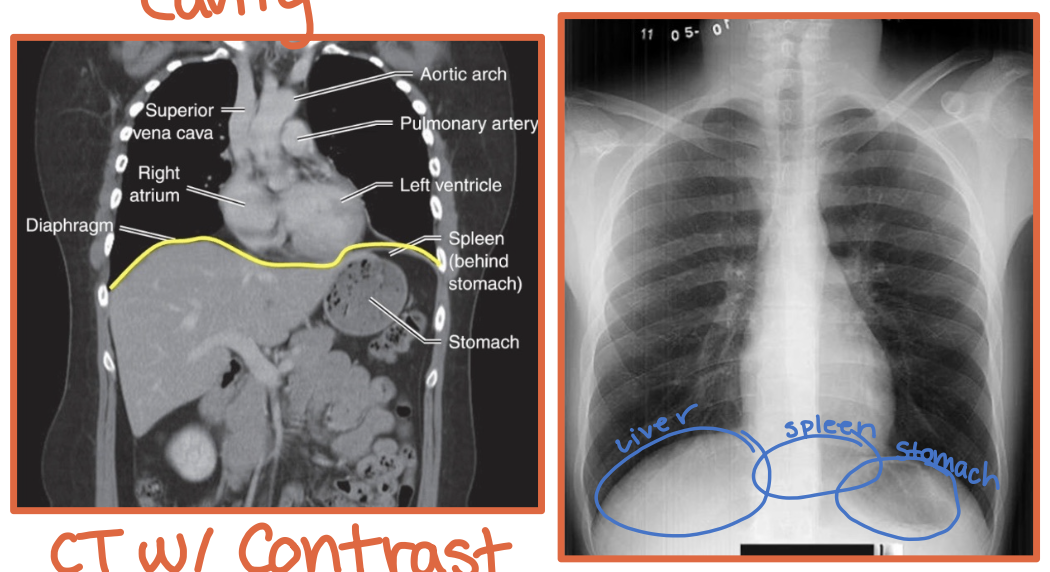

Where is the liver located relative to the hemidiaphragms?

Under the right hemidiaphragm

R + Liver = River

Where is the stomach located relative to the hemidiaphragms?

Under the left hemidiaphragm

Stomach took an L

What is the diaphragm?

A thin curved sheet of muscle separating the thoracic and abdominal cavities